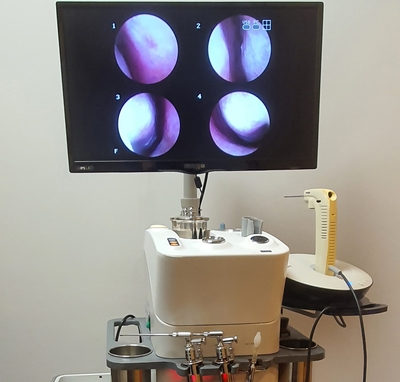

경희미의원 코내시경, 비내시경, 경상코점막의 발적을 관찰하여 2차 세균 감염이 일어나지 않을 경우 점액기로 옮김과 동시에 호전됩니다.통상적으로 증상이 사라지기까지 5~10일 소요됩니다.

경희미의원 진단, 치료를 먼저 10세 여아의 급성 비염 비내시경 치료 전후 사진을 소개합니다.

치료전(좌) → 치료후(우) 여 / 10세, 급성 비염, 2주 치료기간

비염은 정확한 진단이 우선입니다.급성 및 만성 비염, 축농증, 알레르기 비염의 경우 증상이 다를 뿐만 아니라, 코의 내시경 검사 코 점막과 콧물의 양상도 다릅니다.그리고 중이염 여부도 확인해 보도록 합시다.경희미의원은 조재훈 원장이 직접 코내시경을 통해 코 점막의 상태를 확인합니다.주요 치료는 면역 관련 한약이기 때문에 빈번하게 병원을 방문할 필요가 없습니다.